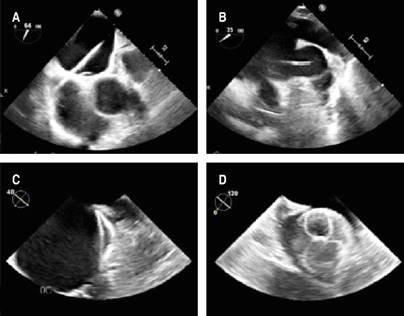

Even though conventional scores showed a low-risk result, it was considered essential to revert to sinus rhythm due to the strong thrombotic component conditioned by the UC and the contraindication for anticoagulation. An electrophysiological study was performed, followed by cryoablation of the four pulmonary veins (Figures 1 and 2), without achieving sinus rhythm, so it was decided to perform non-success electrical cardioversion twice (200 joules). The intervention team decided to perform a wide antral circumferential ablation (WACA) with posterior wall and left atrial appendage isolation, thus successfully achieving arrhythmia jugulation. Due to the hindrance of anticoagulation, after the left atrial appendage isolation, a closure device was placed in the left atrial appendage (Figures 2 and 3). After three months of optimal medical management with apixaban and amiodarone, the patient remained in sinus rhythm, and anticoagulation was discontinued. The patient is free of thrombotic and bleeding events for more than one year after the procedure and after stopping the anticoagulant.

Figure 1: A-D) Cryoablation sequence of the four pulmonary veins. E) Cryoablation of the left atrial appendage after failed cardioversion.